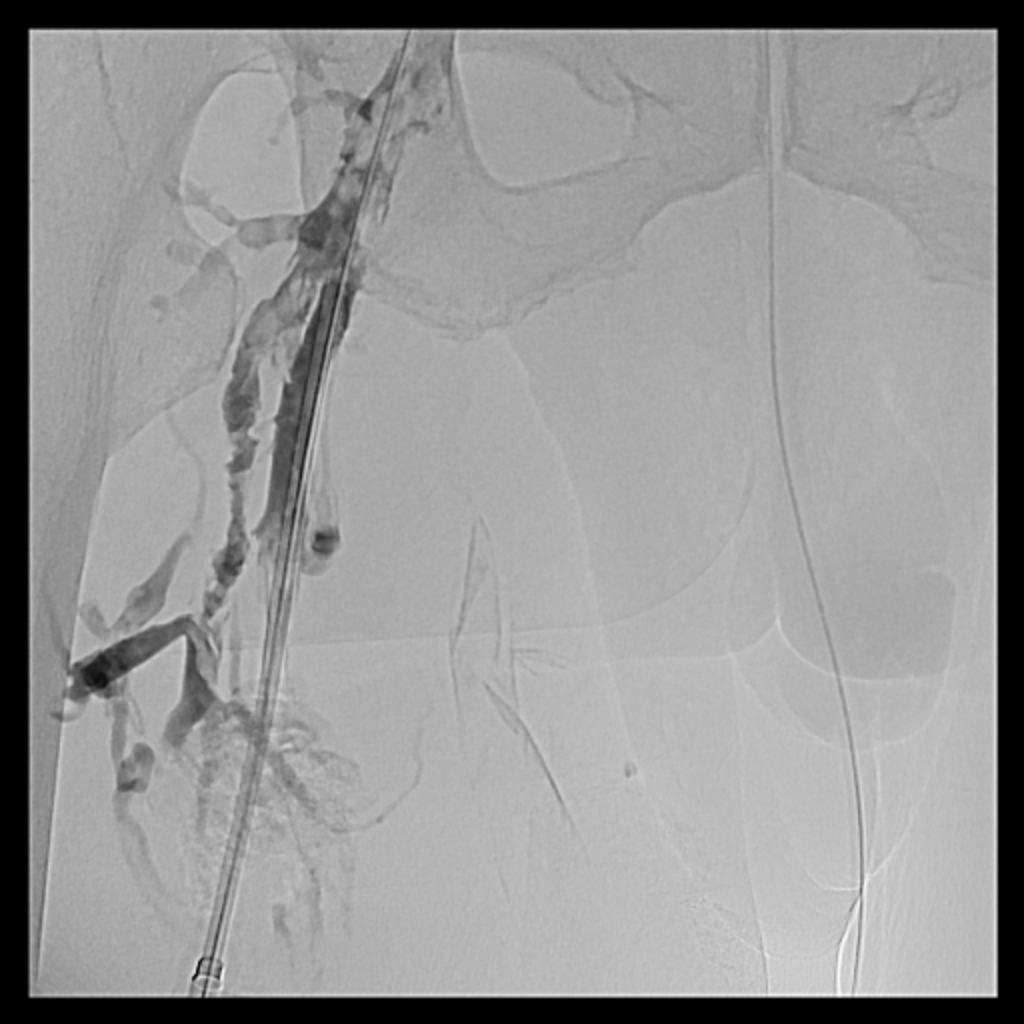

Venous access was obtained and venography confirmed heavy thrombus burden; therefore, the initial 6 Fr sheath was upsized to a 9 Fr sheath. Two Terumo stiff wires were advanced into the IVC to secure stable access. Mechanical thrombectomy using the Boston Scientific AngioJet system was performed from the right iliac vein to the right common femoral vein. During venography, unexpected early arterial opacification suggested an iatrogenic artery-to-vein fistula. Iliac angiography was then performed, revealing a total occlusion of the right common iliac artery with collateral reconstitution. To restore arterial flow and seal the fistula, a contralateral approach was used. A wire successfully crossed the occluded segment into the true lumen, followed by deployment of a covered stent. Final angiography showed complete closure of the fistula and restored antegrade arterial flow without distal embolization. The patient remained hemodynamically stable.